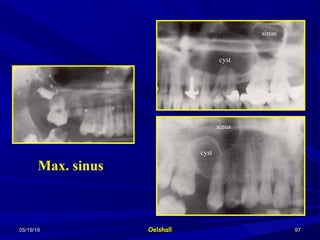

Maxillary sinusMaxillary sinus

Can be misinterpreted for a cystCan be misinterpreted for a cyst

To differentiate:To differentiate:

Check the normal radiographic appearanceCheck the normal radiographic appearance

of the sinus with its septae.of the sinus with its septae.

Take a radiograph of the other sinus toTake a radiograph of the other sinus to

compare.compare.

The radiolucency of the sinus (air filled) isThe radiolucency of the sinus (air filled) is

more than that of cyst (fluid filled)more than that of cyst (fluid filled)

Vitality test.Vitality test.

Max. sinus

cyst

sinus